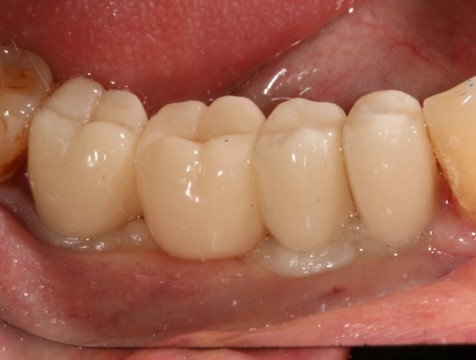

Поэтому после удаления зуба мы ждём, в общей сложности, около 4-8 недель, затем приступаем к имплантологическому лечению. Хотя, иногда бывают ситуации, когда мы делаем синуслифтинг одномоментно с удалением зуба, а сам имплантат ставим попозже:

через 4 месяца: